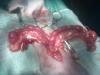

Гектор Опубликовано 25 февраля, 2011 Опубликовано 25 февраля, 2011 Всем привет! Прошу прощения за длительное отсутствие - ездил с ребёнком на соревнования (у меня дочка теннисом занимается). Ну теперь я снова с Вами и в качестве продолжения нашего занимательного диспута попробую выложить новые красочные иллюстрации Вчера на работе выдалась свободная минутка и я зашёл к коллегам в хирургию, а там...как раз идёт операция по удалению матки у собаки! Так что специально для нашего форума и конечно же для моего уважаемого оппонента, предлагаю Вам небольшой, но эксклюзивный фоторепортаж с реально проводимой операции! На приведённых снимках хорошо видно строение матки у собаки, к тому же, чтоб было понятней, я сделал небольшие пояснения непосредственно на фото. Как видно, никаких "яйцеводов", труб и т.п. "извитых образований" длиной 4-10 см. между яичниками и рогами матки нет. В данном случае операция проводилась по поводу эндометрита, т.е. гнойного воспаления матки и надо отметить её (матки) характерный вид при этой болезни. Во-первых увеличение в размере: у такой собаки (в данном случае это йоркширский терьер) диаметр рогов матки в норме не превышает 3-4 мм.(т.е. не толще обычного карандаша), во-вторых форма: наличие характерных сегментарных расширений (как бы "вздутий") рогов матки (в норме рога имеют форму практически ровной трубки с гладкой поверхностью). При этом полость матки заполнена гнойным экссудатом. Данная патология, кстати сказать, встречается очень часто и является опасной для жизни при несвоевременной помощи. У стерилизованных сук её не бывает. Итак: подготовлено "операционное поле" произведён разрез брюшной стенки и проводится электрокоагуляция (остановка кровотечения из разрезанных тканей), при этом рога матки частично выведены из разреза. полностью выведен рог матки и яичник, далее ниже яичника наложат лигатуру и он будет отделён вместе с соответствующим рогом матки. оба яичника отделены и матка полностью выведена из брюшной полости, теперь осталось наложить лигатуру на тело матки выше мочевого пузыря и полностью её удалить. так выглядит полностью удалённая матка а это крупным планом место расположения яичника на конце рога.